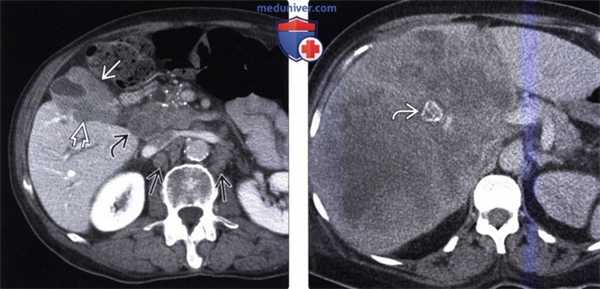

(Слева) На аксиальной КТ с контрастным усилением определяется выраженное неравномерное утолщение стенки желчного пузыря, непосредственная инвазия печени, а также перипанкреатическая/портокавальная и забрюшинная лимфаденопатия. Увеличение лимфатических узлов этих групп является типичным проявлением рака желчного пузыря.

(Справа) На аксиальной КТ с контрастным усилением визуализируется большое гиподенсное образование в печени. Это образование может быть опухолью печени, однако желчный камень в его центре и невозможность визуализации желчного пузыря позволяют предположить, что образование представляет собой рак желчного пузыря с инвазией печени.